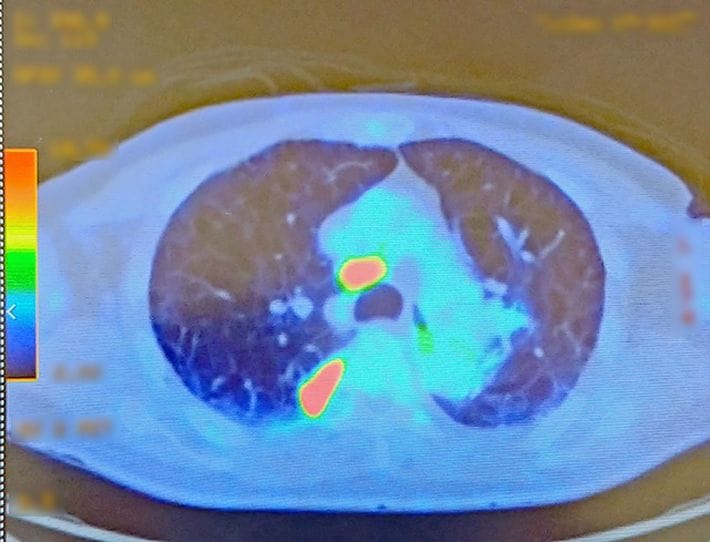

PET-CT検査の画像